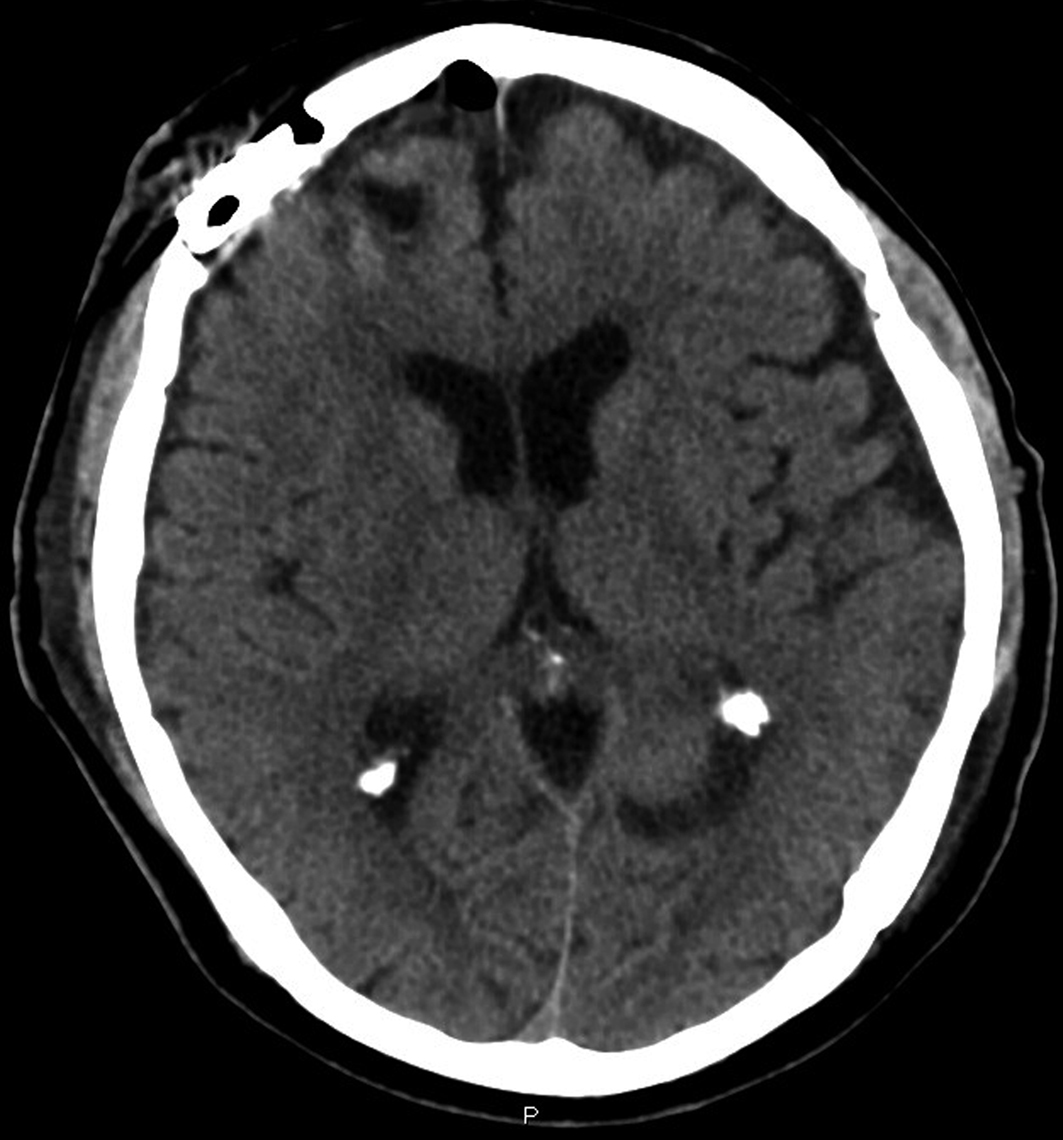

A man, 62 years old, was admitted at our Institute on October 2010 with a recent history of left limbs hypoesthesia and gait instability. Moreover, at the neurological examination a complete cerebellar syndrome associated to hypogeusia and weakness of left arm were found. A brain Magnetic Resonance (MR) with gadolinium showed six distinct cerebral cystic lesions (Fig. 1). A total-body Computed Tomography (CT) was performed with the evidence of multiple right lung nodules, a cystic right renal lesion and irregular prostate margins. The patient did not refer urinary impairment and the serum PSA value was 38.12 ng/dl. Multiple prostate biopsies were obtained and the histology showed adenocarcinoma and a positive immunohistochemical stain for PSA. The right frontal lesion was removed to achieve histologic characterization (Fig. 2). It was demonstrated to be a metastatic prostatic adenocarcinoma with a diffuse immunohistochemical stain for PSA and PSMA (Fig. 3). The patient underwent palliative radiation therapy.

![]() Click for large image | Figure 2. Post-operative brain TC. |